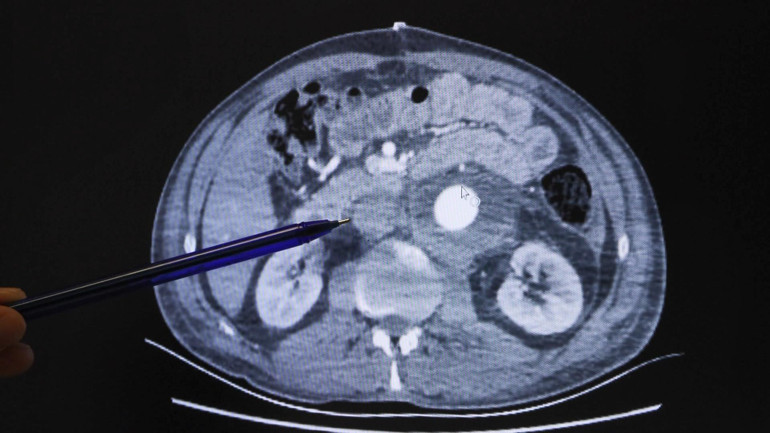

Prof. Dr. Mete Gürsoy, "Hastamızın anevrizması diğer anevrizmalardan biraz farklıydı. Böbrek atardamarlarını da içerdiği için yüksek riskli bir anevrizma olarak tanımlanmıştı. Gördüğümüzde zaten fiziksel özelliklerinden görünümünden Marfan sendromlu olduğunu anladık. Yaptığımız incelemelerde, hastanın karnında yaklaşık 8,5 santim genişliğinde ve böbrek damarlarının üzerine kadar uzanan çok riskli ve cerrahi açısından özel teknikler gerektiren bir anevrizma saptadık. Ekip arkadaşım Dr. Salih Gülen ile beraber böbrek arterlerini özel bir solüsyonla koruyarak, böbreklerinin üstünden itibaren aort damarını yapay damarla değiştirdik" dedi. Kenger'in aort damarının 8,5 santime ulaşmasına rağmen yırtılmamış olmasının çok büyük bir şans olduğuna da dikkat çeken Prof. Dr. Gürsoy, “Hatta hiçbir semptom vermeden tesadüfen saptanmış rahatsızlığı. Cerrahi teknik başarılı olsa da ömrünün geri kalanında diyalize mahkum olabilirdi. Bunu engellemek için özel teknikler kullanılıyor. Dünyanın pek çok merkezinde farklı teknikler kullanılıyor. Biz bu hastada böbrek damarlarını ayırarak böbreğin içine organ koruma solüsyonu verme tekniğini tercih ettik" diye konuştu.